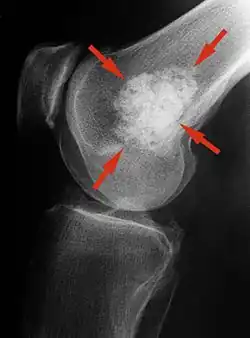

Röntgen

Im Röntgenbild stellt sich das klassische Enchondrom als zur Knochenachse längliche, ovaläre Läsion zentral im Markraum langer Röhrenknochen dar. Eine exzentrische Lage schließt ein Enchondrom jedoch nicht aus. Das Zentrum der Läsion liegt meist in der Metaphyse oder in der distalen Diaphyse eines Röhrenknochens. Ein kleiner oder kurzer Knochen kann vollständig ausgefüllt sein. Typisch für Enchondrome ist eine Ausdünnung der Kortikalis des Knochens von innen, das sogenannte Scalloping und im Falle einer Expansion über das Volumen des Knochens hinaus die Neubildung der Kortikalis (Neocortex). Eine Periostreaktion wird jedoch praktisch nie beobachtet. Das Erscheinungsbild eines Enchondroms wird des Weiteren hauptsächlich vom stark variierenden Ausmaß der Verkalkungen der primär knorpeligen Tumormatrix geprägt: diese können punktförmig, ring- und bogenförmig („rings and arcs“) und flockig sein. Oftmals imponiert das Bild Popcorn-artig. Die Verkalkungen treten häufiger und ausgeprägter in den langen Röhrenknochen auf, während die Läsionen in den kleineren Knochen der Finger und Füße weniger verkalken. Das Röntgen-Bild erfasst sicher nur die Verkalkungen und das Scalloping, so dass das wahre Ausmaß eines nur gering verkalkten Enchondroms mit dieser Methode unterschätzt werden kann. Verschwinden von vormals verkalkten Arealen innerhalb eines Enchondroms im Verlauf muss als Hinweis auf eine Entartung gedeutet werden.[2]